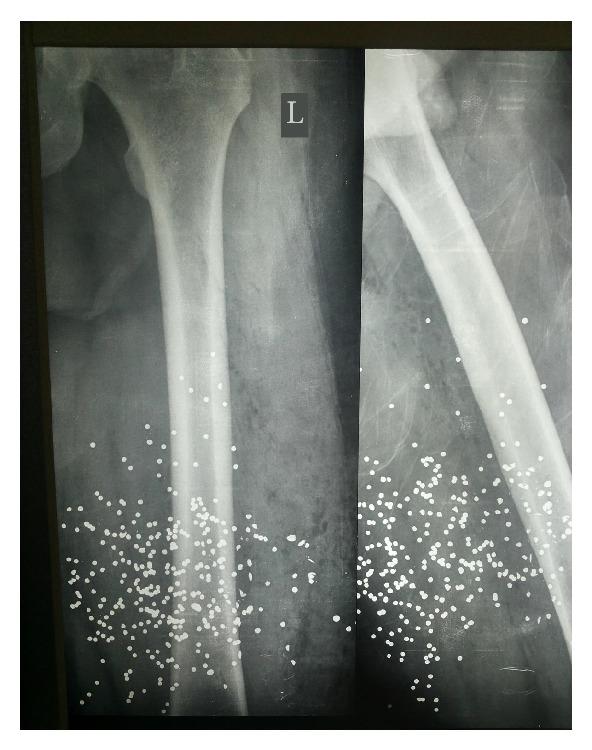

We report a case of a 42-year-old male patient who was transferred to our emergency department suffering from a gunshot wound in his left lateral thigh. The patient was haemodynamically stable, and the physical examination of the abdomen and thorax was unremarkable. There was no obvious exit point and there were no other injuries. The radiologic control of the left thigh showed an intact femur and multiple pellets within the adjacent soft tissues. Routine X-ray evaluation of the thorax revealed a small-sized round object of metal density-possibly a migrated pellet-in the proximity of the right heart atrium. Computed tomography imaging confirmed this finding and showed no other cardiac or mediastinal injury. Ultrasonography of the heart was unremarkable as well. The patient was managed conservatively for the discovered pellet, and remained asymptomatic throughout the entire hospital stay, and 6 months after the discharge. Pellet migration or embolism should be suspected in any gunshot victim without a corresponding exit wound or when the signs and symptoms do not correlate with the suspected course of the missile. Conservative management remains the first choice in asymptomatic patients, although close monitoring at first and regular observation after discharge are indicated.

我们报告一例42岁男性患者,因左大腿外侧枪伤被转至我院急诊科。患者血流动力学稳定,腹部和胸部体格检查未见异常。没有明显的出口点,也没有其他损伤。左大腿的影像学检查显示股骨完整,相邻软组织内有多个弹丸。胸部常规X线检查发现右心房附近有一个金属密度的小圆形物体——可能是一枚迁移的弹丸。计算机断层扫描成像证实了这一发现,且未显示其他心脏或纵隔损伤。心脏超声检查也未见异常。患者因发现的弹丸接受保守治疗,在整个住院期间及出院后6个月均无症状。对于任何没有相应出口伤口或体征和症状与疑似导弹行径不相关的枪伤受害者,都应怀疑弹丸迁移或栓塞。对于无症状患者,保守治疗仍是首选,尽管起初需密切监测,出院后也需定期观察。